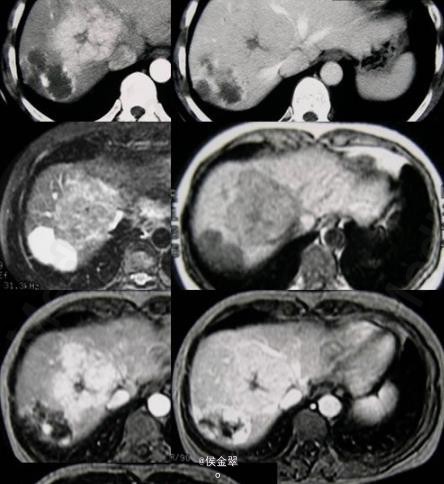

临床一例肝脏 FNH及血管瘤患者

患者女,35岁,因上腹部疼痛1月前来就诊,无肝炎、肝硬化病史

上腹部疼痛,其余正常 辅查CT

肝脏 FNH及血管瘤 处理:手术切除血管瘤